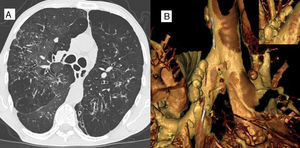

Paciente de 36años, de sexo masculino, ex tabaquista (14 paquetes/año) candidato a trasplante pulmonar por bronquiectasias adquiridas no fibrosis quística. La radiografía simple de tórax presenta datos de hiperinsuflación pulmonar, junto con imágenes radiolúcidas compatibles con bronquiectasias. La tomografía axial computarizada de tórax confirma la presencia de bronquiectasias y muestra imágenes aéreas en el mediastino sugestivas de divertículos traqueobronquiales (fig. 1A). Su reconstrucción virtual muestra múltiples imágenes saculares en ambos bronquios fuente (fig. 1B). La imagen superior derecha permite observar el cuello de los divertículos. La endoscopia virtual reveló además pequeñas depresiones mucosas correspondientes a los orificios diverticulares.

Los primeros reportes de esta condición referían una prevalencia de 0,09-0,5%. Recientemente, en una serie de 503 fumadores y otra de 200 adultos sin enfermedad pulmonar su prevalencia fue del 45 y 41%, respectivamente1,2. El tamaño de los divertículos bronquiales fue pequeño (de 1 a 3mm). El motivo de la presentación es mostrar imágenes de divertículos bronquiales bilaterales de gran tamaño (10 a 13mm de diámetro) mediante la reconstrucción tridimensional de tomografía computarizada. Estas imágenes no habían sido observadas en la radiografía simple de tórax.